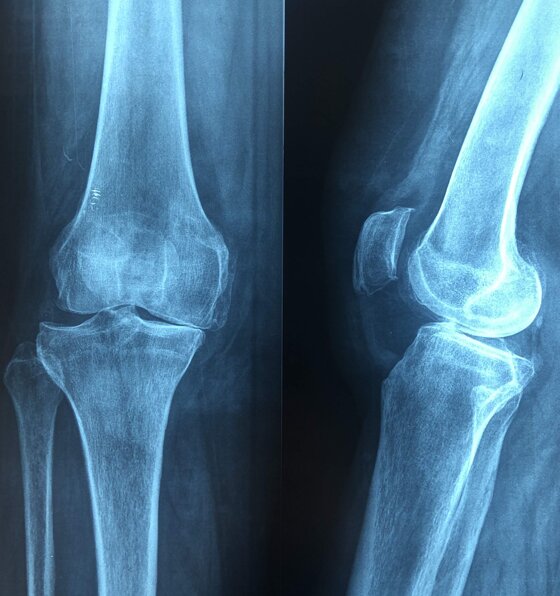

A sinistra radiografie pre-operatorie il AP e LL che evidenziano una grave gonartrosi diffusa con presenza di osteofiti periarticolari e deformità associata (ginocchio varo).

A destra radiografia post-operatoria in AP di intervento chirurgico di artroprotesi di ginocchio cementata, unico trattamento possibile con pz che presentava dolore continuo e zoppia. Ho utilizzato una protesi con risparmio del legamento crociato posteriore (CR) chiamata Persona proprio perché altamente anatomica, cioè molto rispettosa dell’anatomia del ginocchio del singolo paziente